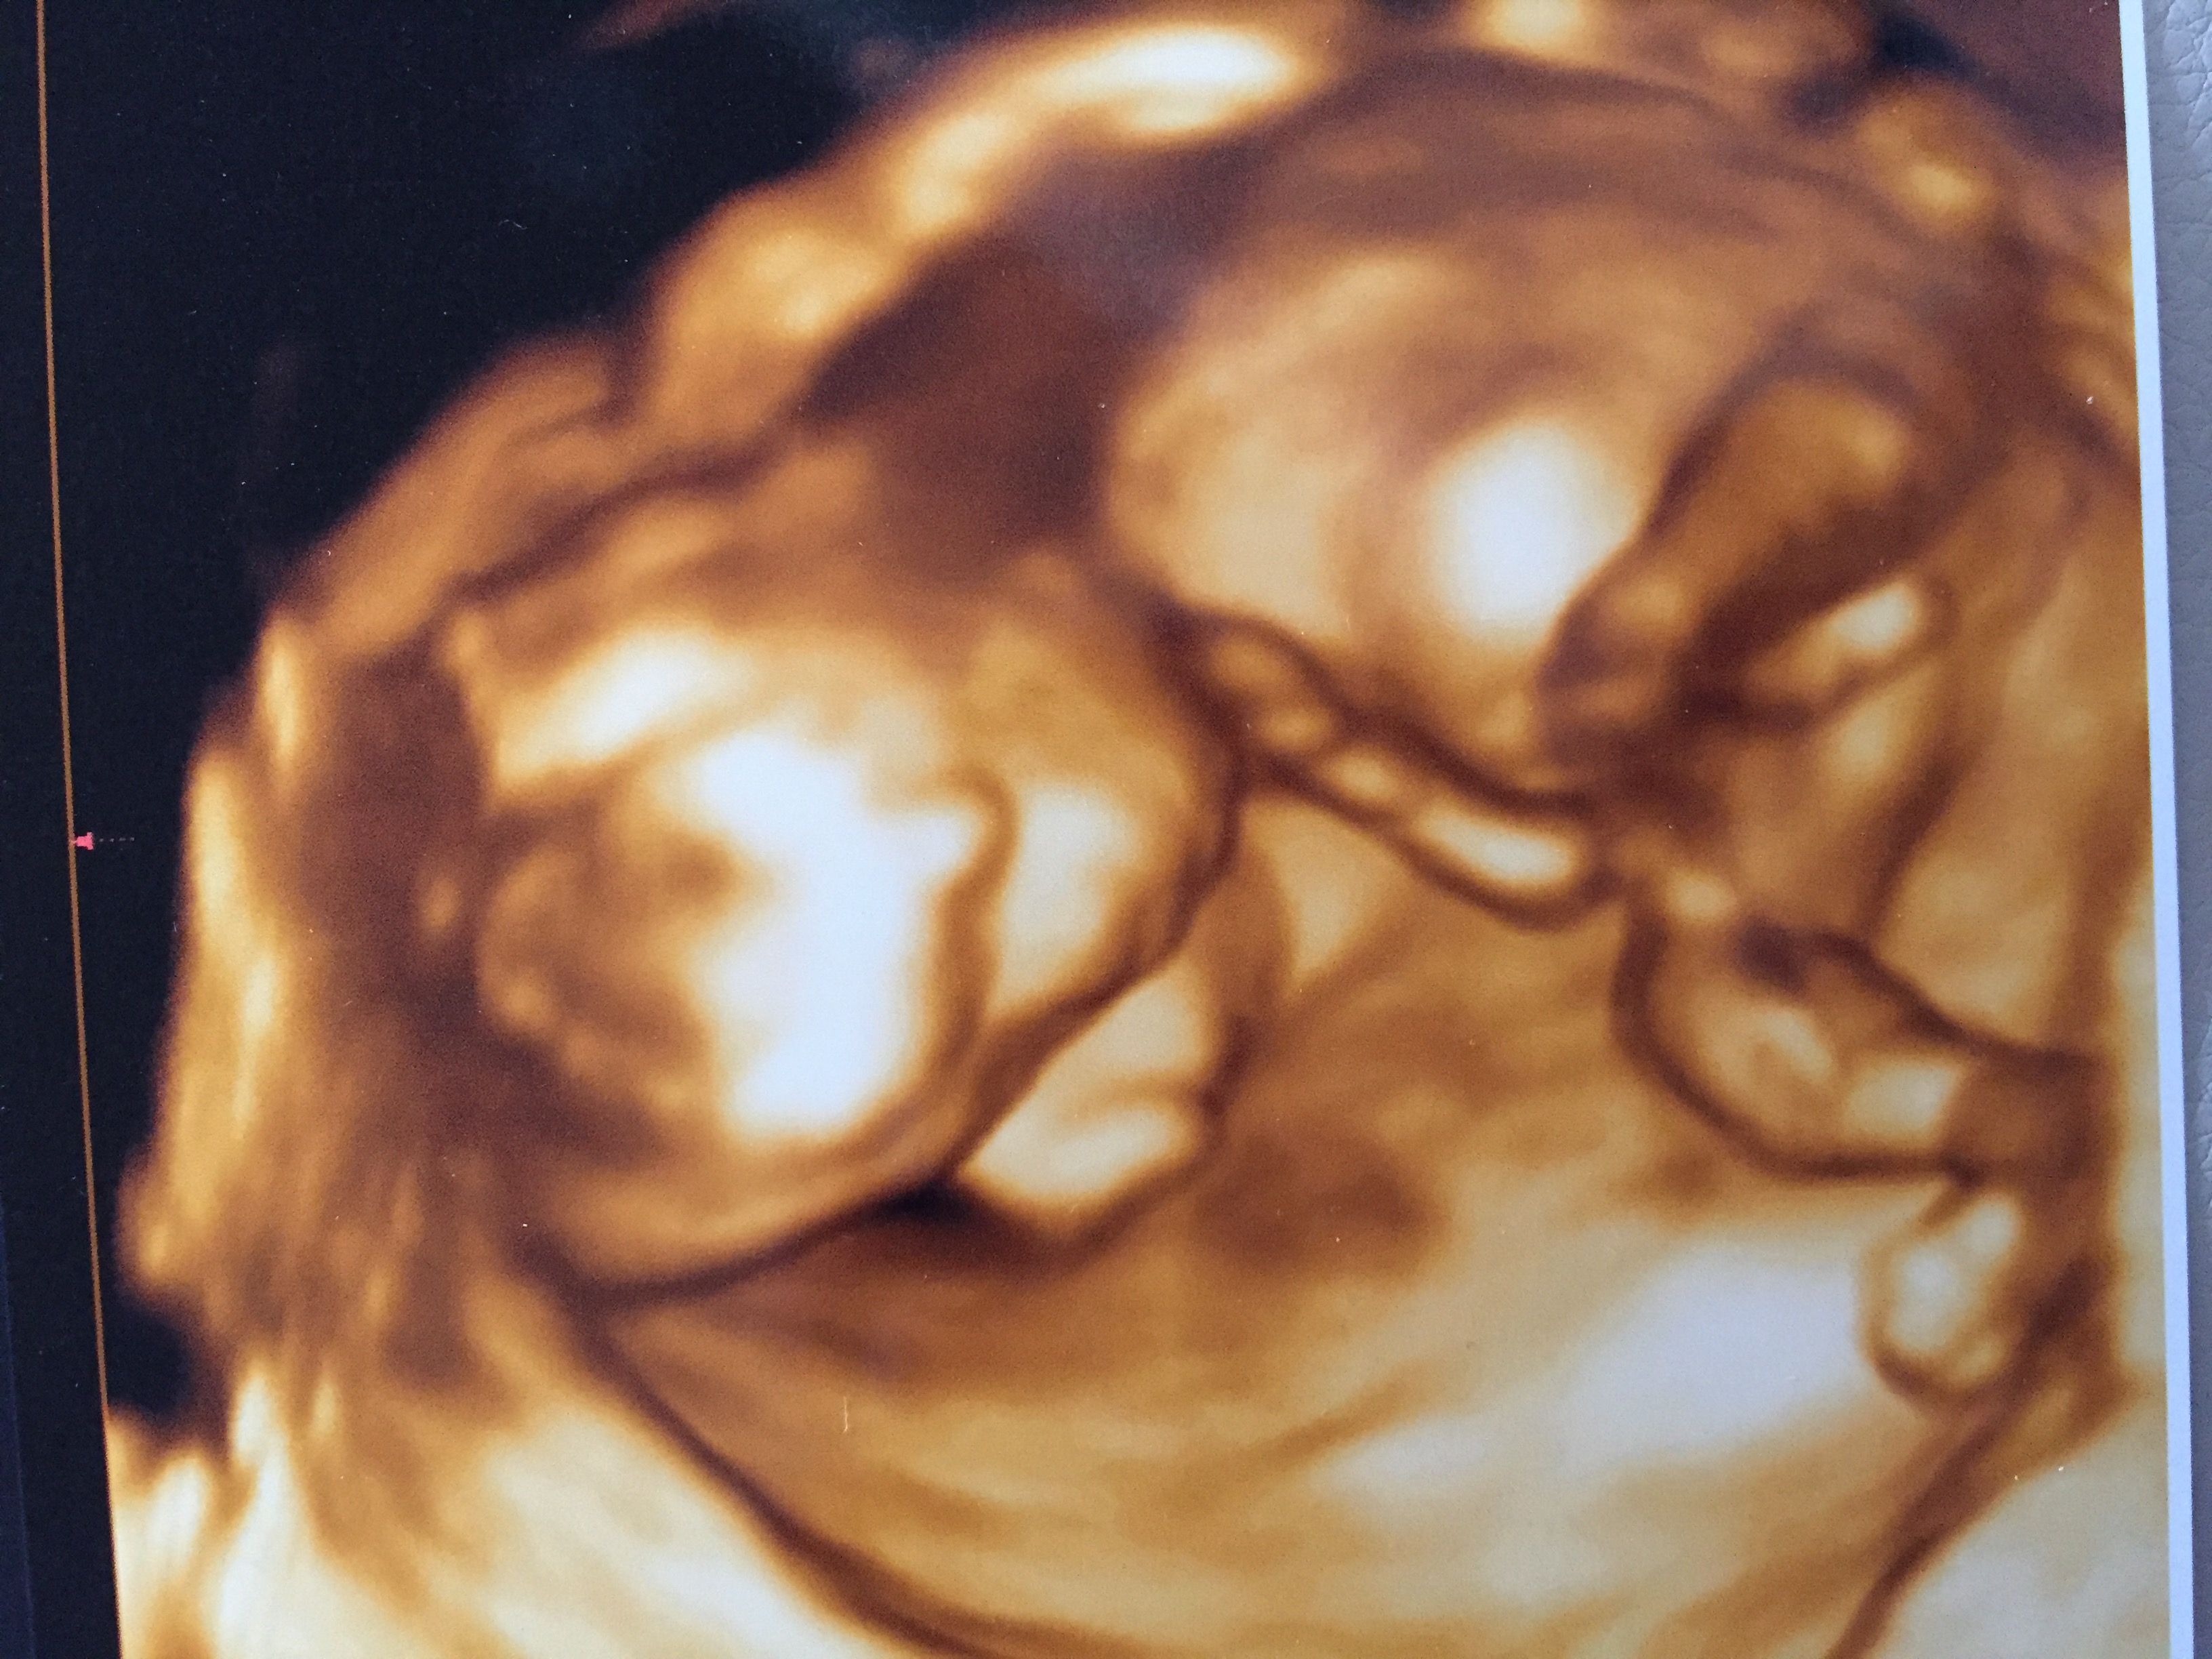

16 Week 3d Ultrasound

16 week 3d ultrasound. Youll also get to hear the heartbeat and youll see your little one bouncing around inside your belly. What it would look like you might just feel your baby move when youre 16 weeks pregnant. And in happy news your risk of miscarriage is less than 1 after seeing a normal 16 week ultrasound. Jeniffer baby 16 weeks 3d 4d ultrasound 3d 4d ultrasound video duration.

Room is big enough to seat the whole family. Youll probably have a four month prenatal visit around the time youre 16 weeks pregnant. 3d ultrasound picture of baby at 16 weeks pregnant. 16 weeks pregnant lifestyle.

Find out whats happening during this important stage of your journey. Inside your 16 weeks pregnant belly baby is listening to your voice thanks to tiny bones forming in their ears. In your 16 week pregnant ultrasound your doctor will probably be able to determine your babys gender. Your 16 week fetus is growing hair lashes and eyebrows and their taste buds are forming.